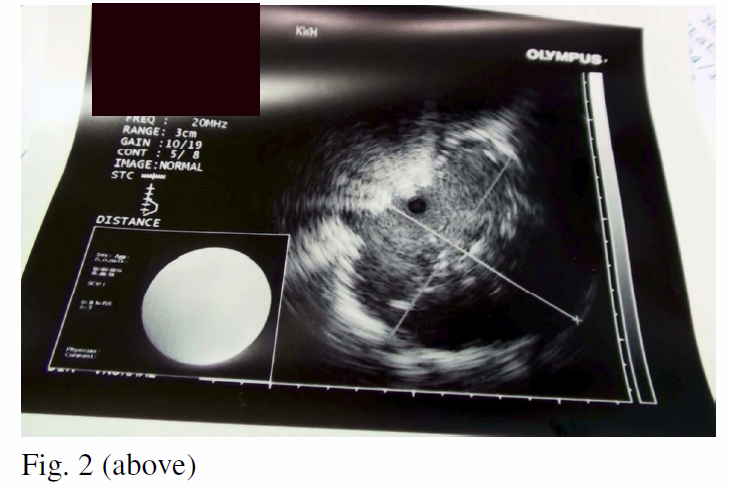

In order to get a better histological sample of the tumour for EGFR activating mutation direct DNA sequencing study, various options of diagnostic procedures have been considered. These include repeating closed pleural biopsy but its yield remains low. Medical pleuroscopy was then not available in our hospital. The yield of bronchoscopic transbronchial lung biopsy is relatively low (~40%) given the peripheral location of the tumour. Although its yield could be improved with fluoroscopic guidance, we do not perform fluoroscopy in our hospital. CT-guided transthoracic needle aspiration can be associated with complications such as iatrogenic pneumothorax (~15-43%) and haemorrhage (~5-17%), while its yield can vary and depend very much on the experience of radiologists. VATS open lung biopsy would be the most accurate procedure but it is more invasive and costly. It was not chosen because of the confirmed advanced staging of the disease.With the availability of endobronchial ultrasound (EBUS), we have explored the clinical application of miniprobe radial

EBUS guided transbronchial lung biopsy. With the guidance of radial EBUS probe through the working channel of a regular therapeutic bronchoscope, a lesion measured 1.67cm x 1.89cm (Fig. 2) was located distal to the RB3a subsegment. Guidesheath guided brush cytology and transbronchial biopsy yielded adenocarcinoma. Subsequent mutation study showed a 15 bp deletion (2235-2249) of the exon 19, compatible with an exon 19 EGFR activation mutation.